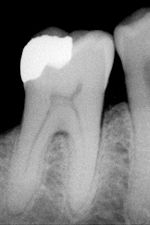

Most dental restorations involve the removal of enamel. Frequently, the purpose of removal is to gain access to the underlying decay in the dentin or inflammation in the pulp. This is typically the case in amalgam restorations and endodontic treatment.

Nonetheless, enamel can sometimes be removed before there is any decay present. The most popular example is the dental sealant. The process of placing dental sealants in the past involved removing enamel in the deep fissures and grooves of a tooth and replacing it with a restorative material. Presently, it is more common to only remove decayed enamel if present. In spite of this, there are still cases where deep fissures and grooves in enamel are removed in order to prevent decay, and a sealant may or may not be placed depending on the situation. Sealants are unique in that they are preventative restorations for protection from future decay and have shown to reduce the risk of decay by 55% over 7 years.